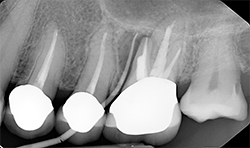

Periapical radiographs (Figs. 8A, 8B) show that radiolucent area around the mesial root of #14 and missing lamina dura. The apical lesion is close to the floor of the left maxillary sinus.

CBCT (Figs. 9A, 9B) reveals the lesion extends from the buccal cortex to the palatal cortex with furcation involvement and involves the palatal root. Mucosal thickening is noted along the floor of the left maxillary sinus, suggesting odontogenic origin. Tooth extraction would be recommended.

FIg. 9A

Fig. 9B